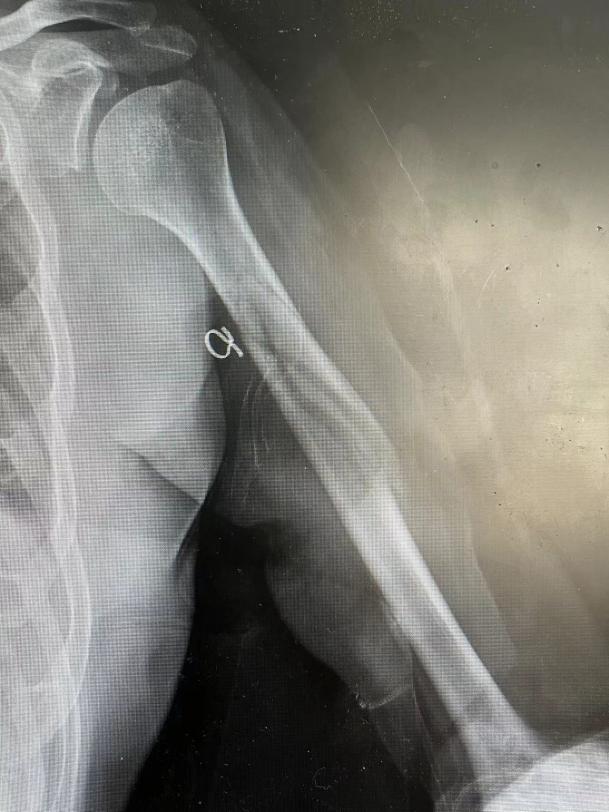

第一次手法整复+小夹板固定复查,骨折端成角畸形纠正,但游离碎骨块对位对线欠佳

再次予以手法整复,同时调整压垫位置,复查可见碎骨块位置较前好转

此时骨折端及碎骨块位置已较前明显好转,但患者及家属仍表示不满意,在透视下再次进行手法整复及压垫调整后复查DR,骨折端及碎骨块位置对位对线较前好转